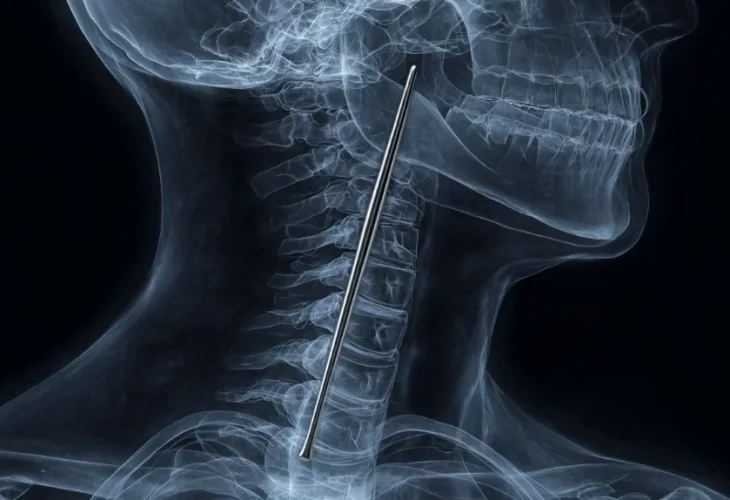

בצילומים נראה בבירור מקל מתכתי שתקוע בגרונו, ומחולל את כל הכאב שהרגיש. "המקל היה באורך של כמעט 12 סנטימטרים, וכששאלנו על כך המטופל ענה באגביות שהוא בלע את זה בטעות לפני שמונה שנים, בזמן שאכל כנראה תחת השפעת אלכוהול".